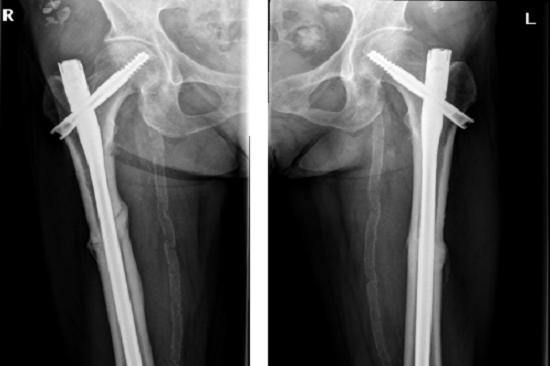

李占玉醫生團隊當時嚇了一跳,輕微暴力就能引起雙側股骨干骨折,這比較少見,肯定是病理性骨折,首先想到的是腫瘤所致,追問病史,患者否認有腫瘤病史,但有系統性紅斑狼瘡30多年,口服福善美5年,但已經停藥2年,在摔倒前有左側大腿根疼痛。根據病人的病史、體征和X線片所見,我們診斷為非典型股骨骨折,然后行髓內釘內固定術,術后8個月骨折愈合(圖2)。

圖2:髓內釘固定骨折,術后8個月,骨折愈合